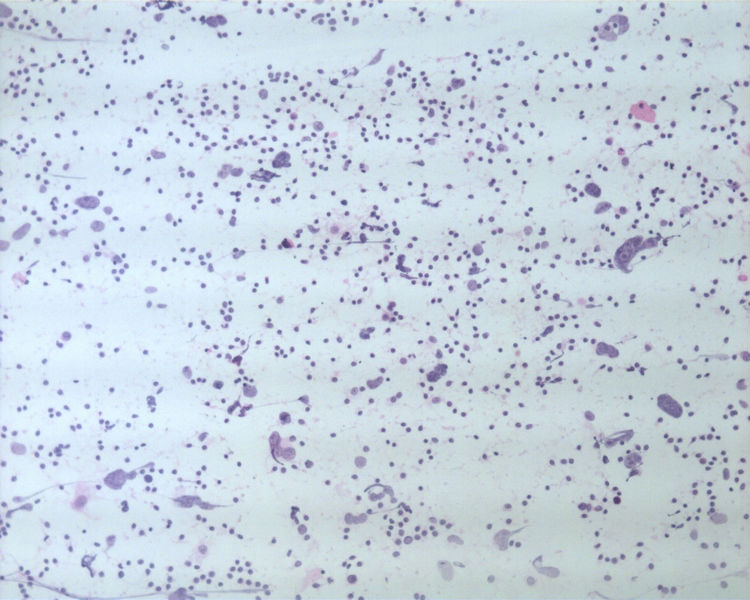

• 男性,50岁,右锁骨上淋巴结穿刺。图1

图1

• 男性,50岁,右锁骨上淋巴结穿刺。图2

图2

• 男性,50岁,右锁骨上淋巴结穿刺。图3

图3

基本都是淋巴细胞背景中散在异形非常明显的细胞。细胞无成巢现象。

这是一例我以前穿刺的病例。当时涂片发现淋巴细胞的背景中散在大而非常异形的细胞。细胞没有成巢现象。